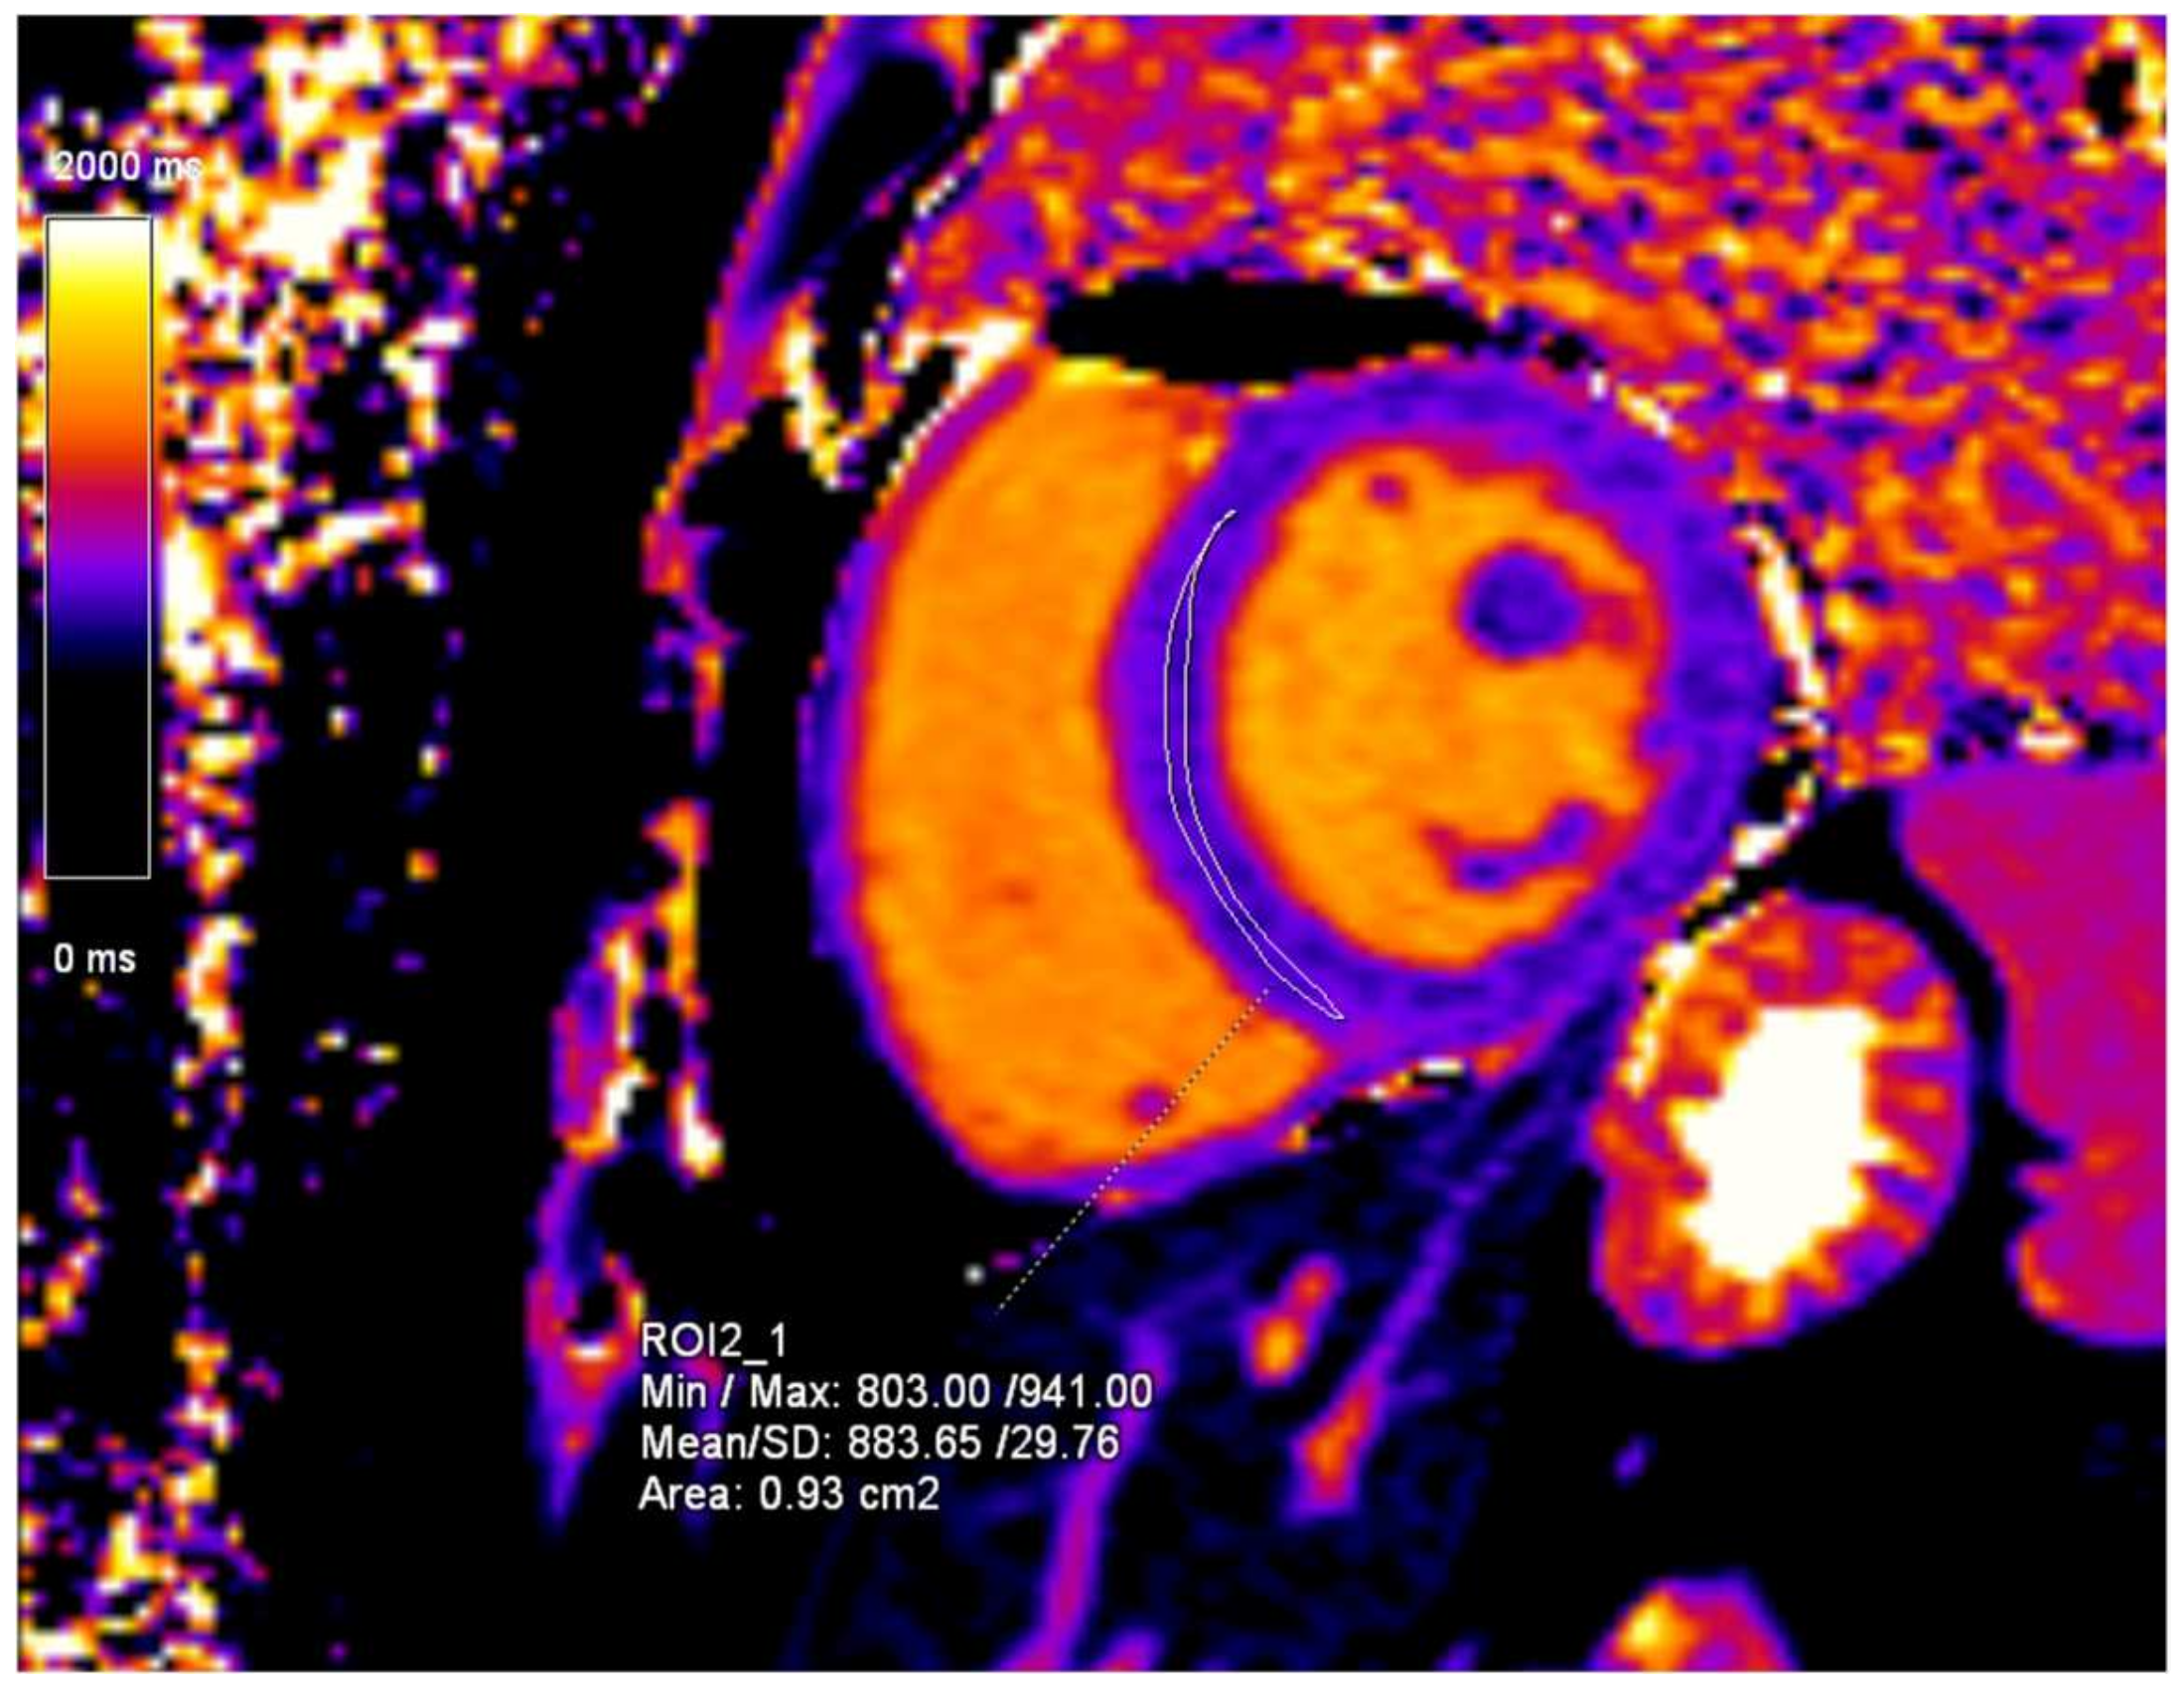

2. Case Presentation